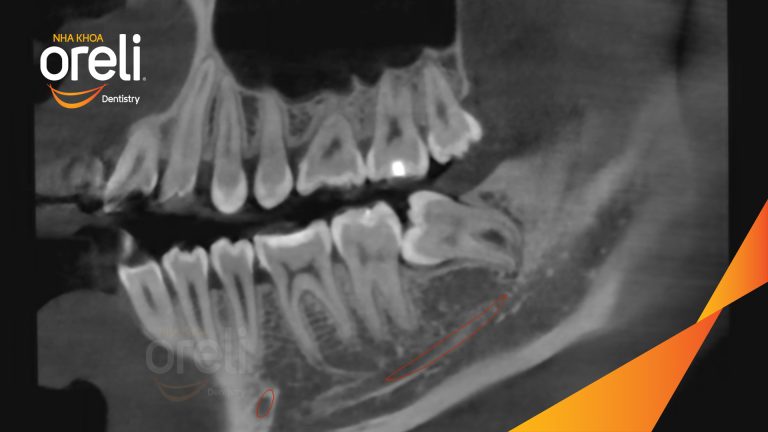

Ca nhổ răng khôn ảnh hưởng răng bên cạnh – Điều trị tại Oreli

Nhổ răng khôn

Mọc lệch